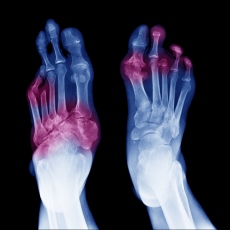

Gangrene is the death of tissues in your body. It happens when a part of your body loses its blood supply. Gangrene can happen on the surface of the body, such as on the skin, or inside the body, in muscles or organs. Causes include:

Skin symptoms may include a blue or black color, pain, numbness, and sores that produce a foul-smelling discharge. If the gangrene is internal, you may run a fever and feel unwell, and the area may be swollen and painful.

Gangrene is a serious condition. It needs immediate attention. Treatment includes surgery, antibiotics, and oxygen therapy. In severe cases an amputation may be necessary.